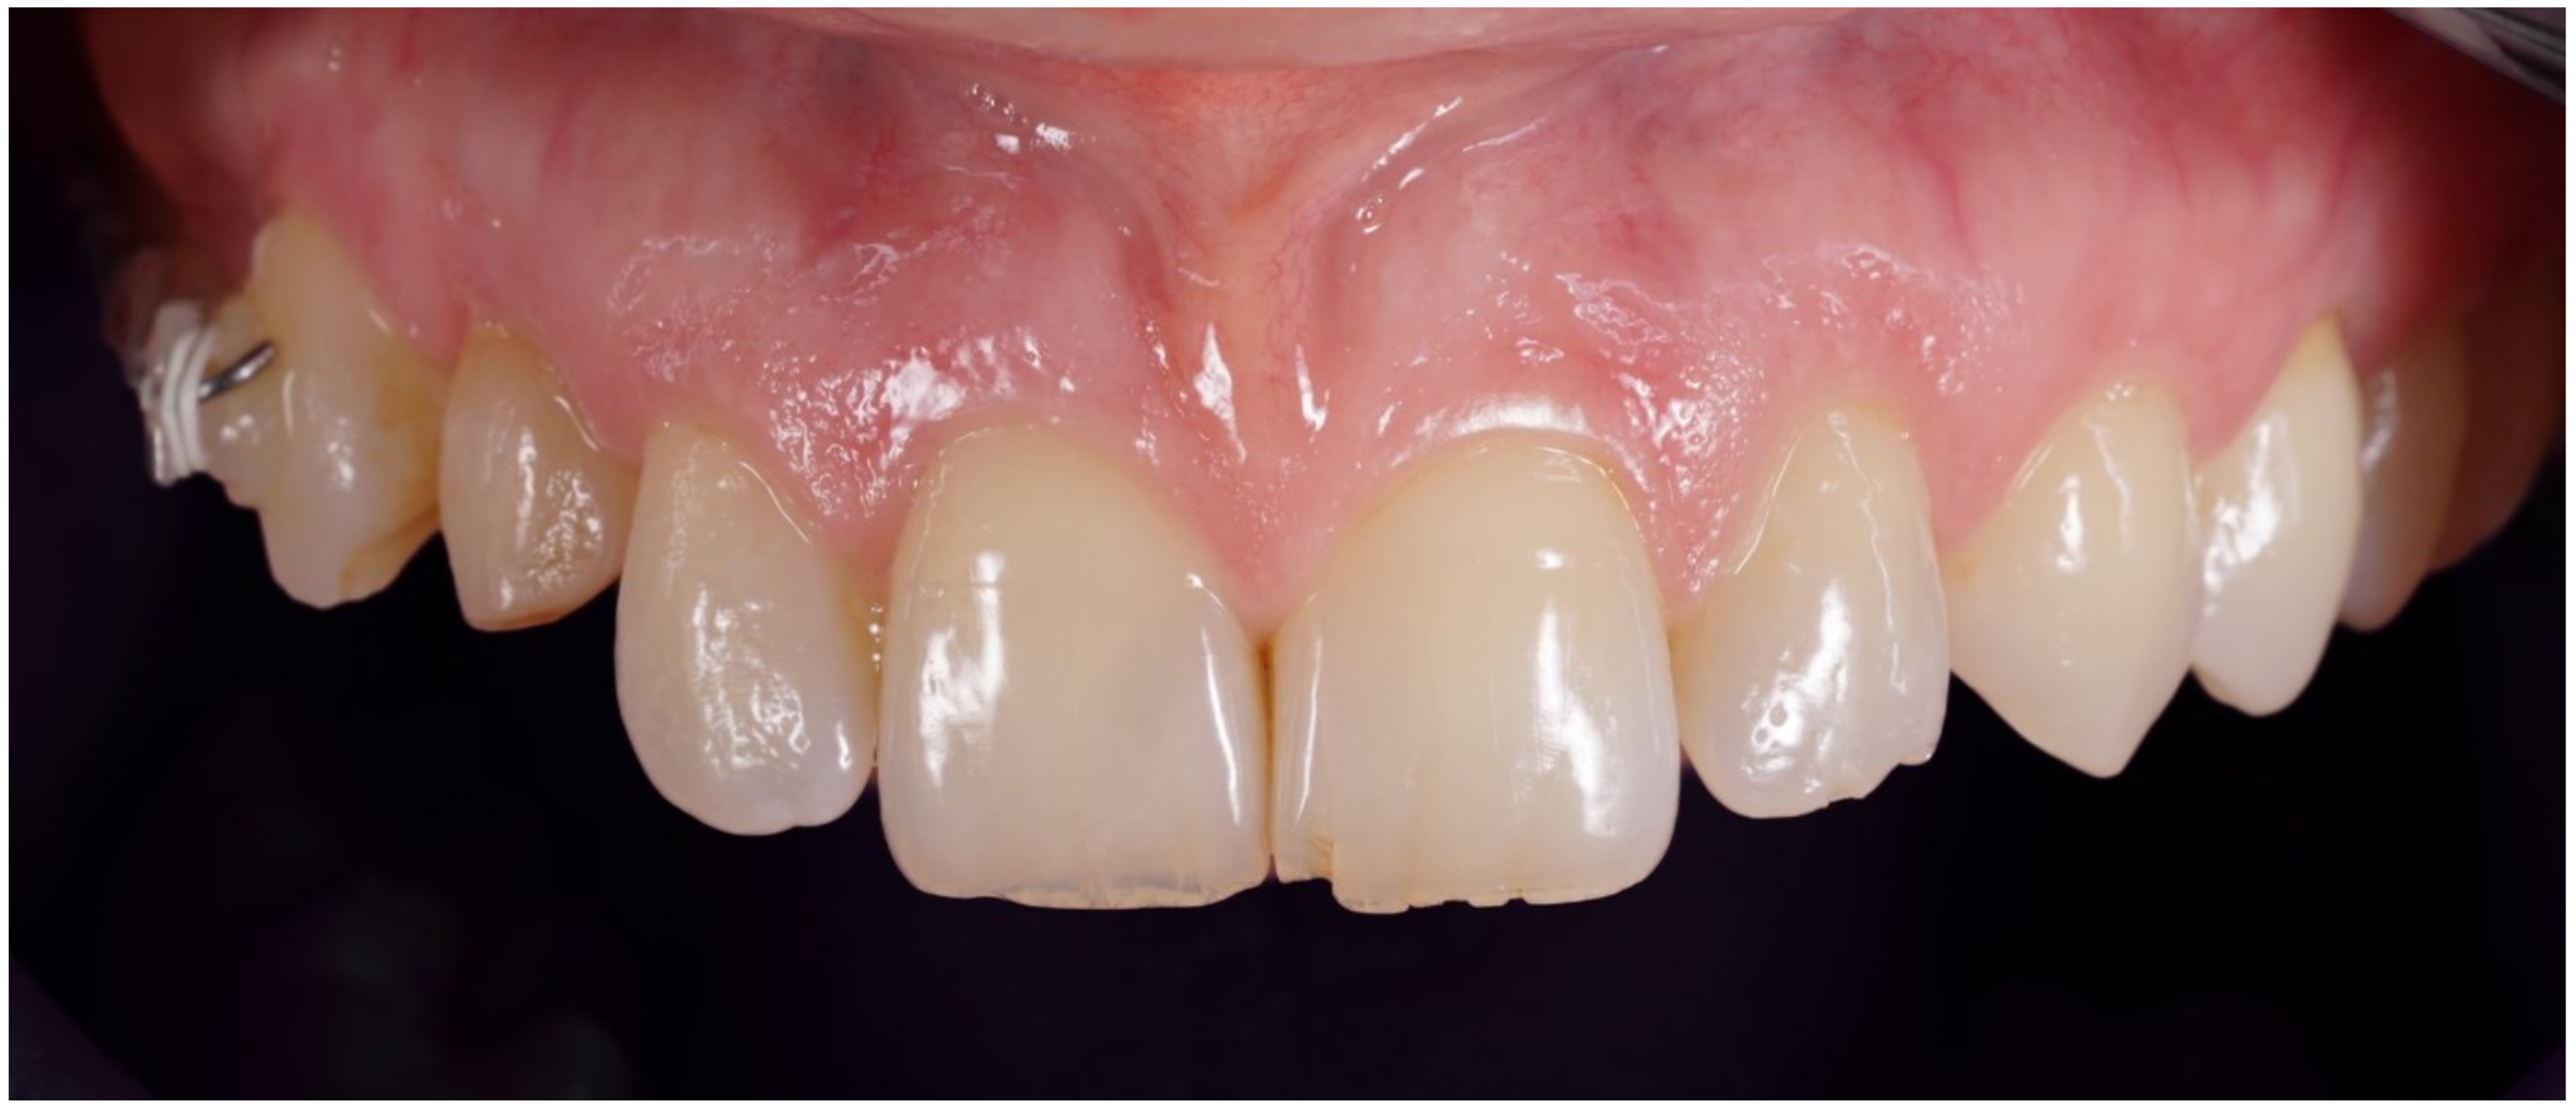

Figure 1.

Preoperative frontal view.